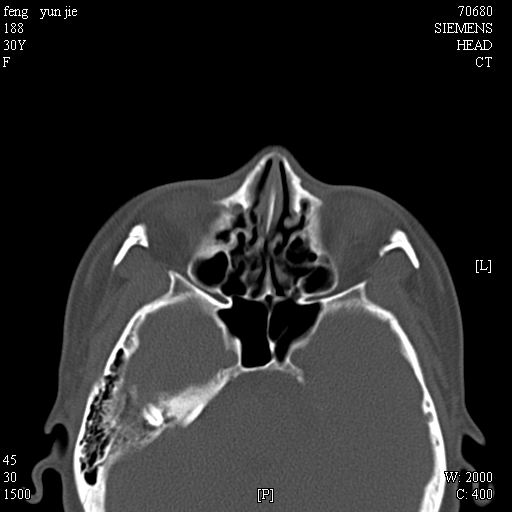

女,37岁,多年前鼻骨骨折过,现在穿刺有炎性分泌物

1)左侧鼻骨骨折(陈旧性)。2)双侧额窦及双侧筛窦炎症,伴右侧额筛窦黏液囊肿突入右侧眼眶。

额窦粘液囊肿(右侧水平额窦突入眶内上方)可能性大

是黏液囊状还是淋巴瘤?建议结合穿刺细胞学检查。